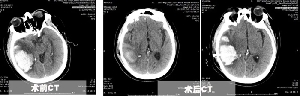

精準(zhǔn)微創(chuàng)手術(shù),重癥腦出血患者快速康復(fù)

近日,患者王先生將一面錦旗親手送給神經(jīng)外一科李永濤主任?;颊咄跸壬?,62歲,體重200余斤,糖尿病、冠心病、腦梗塞病史3年余,長(zhǎng)期口服二甲雙胍、阿司匹林、瑞舒伐他汀等藥物,病情控制一般。7月8日,患者突發(fā)頭痛頭暈,出現(xiàn)一側(cè)肢體偏癱、意識(shí)障礙,急診行顱腦CT提示枕頂葉大面積腦出血,血腫量超過(guò)50ml,有手術(shù)指征。據(jù)